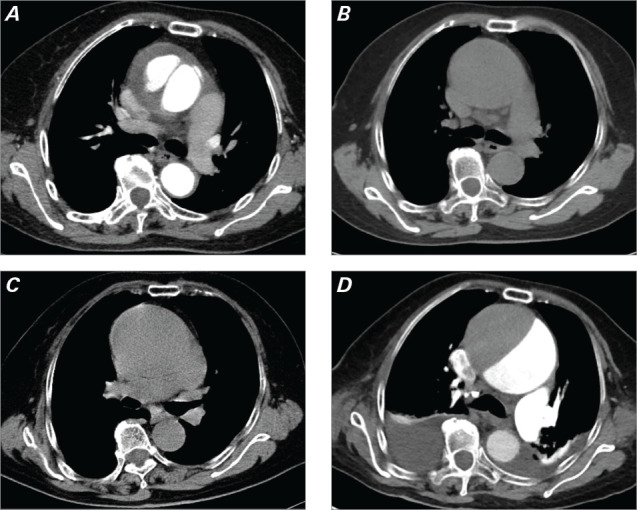

Acute type A aortic dissection is a catastrophic cardiovascular event characterized by severe pain and hemodynamic instability. The standard of care is emergency surgery, which, despite its benefits, carries substantial perioperative risks. Conservative management is an alternative approach reserved for older patients with clinically significant comorbidities or for whom surgical risk is prohibitive and perioperative mortality may outweigh potential benefits. The case is presented of a 75-year-old patient who opted for conservative management and has been followed up with favorable outcomes for 9 years since the index event.